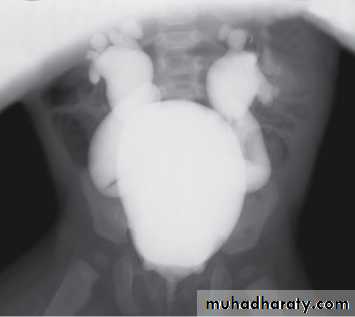

The VCUG:

the definitive examination

to diagnose and grade reflux and establish reversible causes

must include a voiding phase:

in some cases, reflux may be seen only during the elevated intravesical pressures associated with micturition.

in visualizing the urethra, may allow the diagnosis of outflow obstruction to be made (e.g., posterior urethral valves).

MCUG